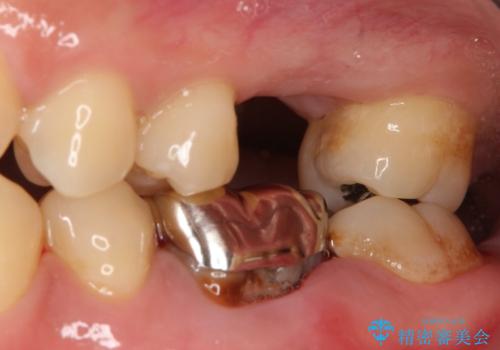

- 銀歯の下が大きな虫歯になり、保存困難のためその後の治療計画について悩まれていた患者様です。

患者様と相談し、親知らずを用いて歯牙移植を行いました。

- 外科手術のため、術後に痛みや腫れ、違和感を伴います

- 適応範囲に制限があります(健康な親知らず・移植歯が必要など)

- 移植歯が生着しない可能性があります

- 予後が不安定で歯によっては長く持たない可能性があります